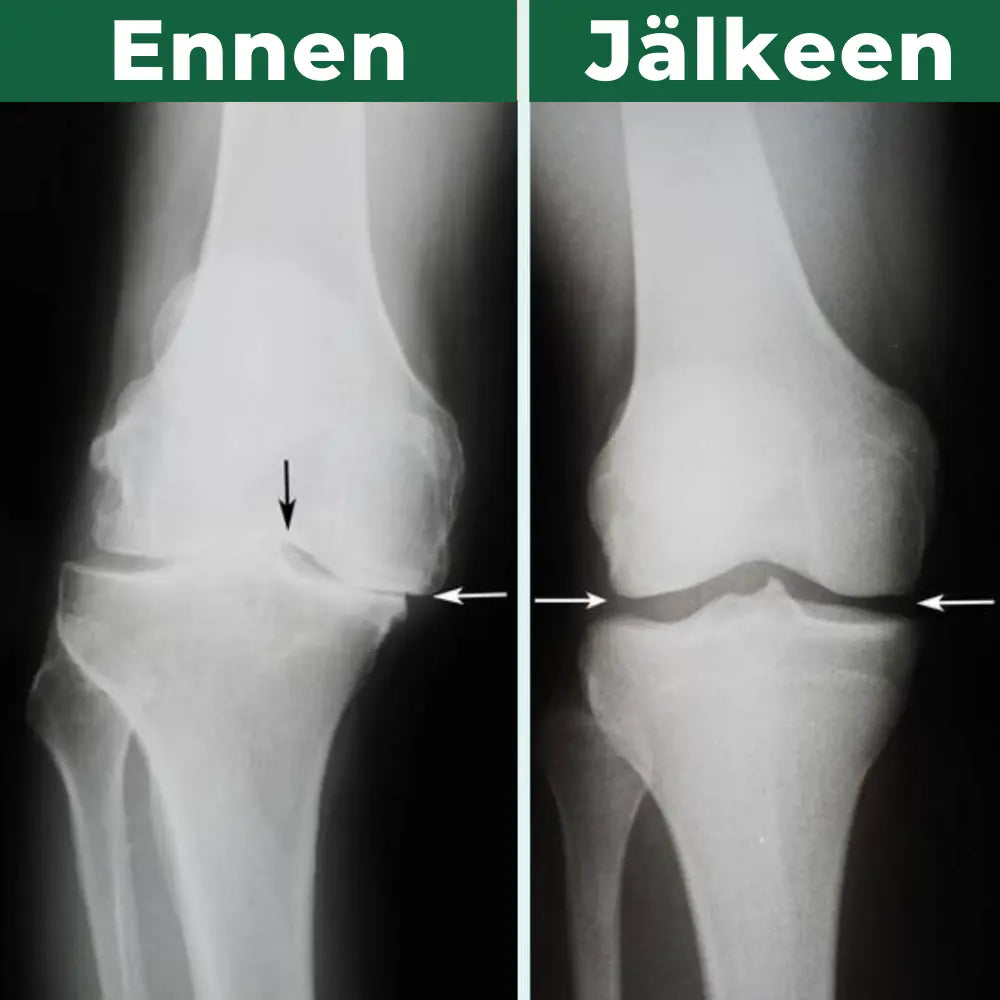

Asiakkaiden onnistumiset puhuvat

enemmän kuin sanat!